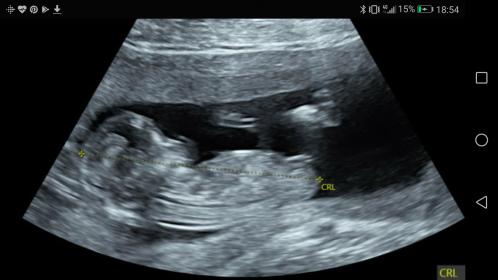

Hi all! I just had my 12 week scan at 12w5d and the tech seemed quite convinced it was a girl (much to my complete surprise because I was sure I'd just have another boy). I've been researching a bit and it definitely seems girly but is it too early to tell really? Is there a chance it will rise? Attachment 39149